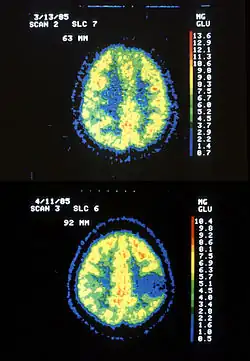

Im PET-Scan des Glucose-Stoffwechsels (FDG-PET) stellt sich das Astrozytom hypometabolisch dar („kalter Knoten“, das heißt, es ist Gewebe mit vermindertem Stoff- und Energieumsatz). Entdifferenzierungen innerhalb des Tumors führen gelegentlich zu malignen Zwischenstufen, die dann im PET-Bild als „hot spots“ (Gewebe mit erhöhtem Stoff- und Energieumsatz) innerhalb des „kalten Knotens“ erscheinen können.